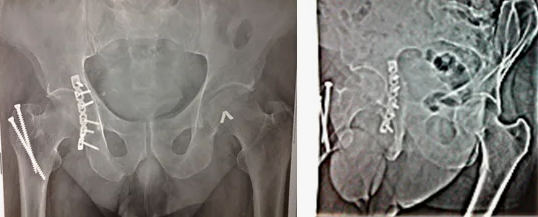

В случае перелома шейки бедра компания МосРентген Центр госпитализирует в Склиф для эндопротезирования.